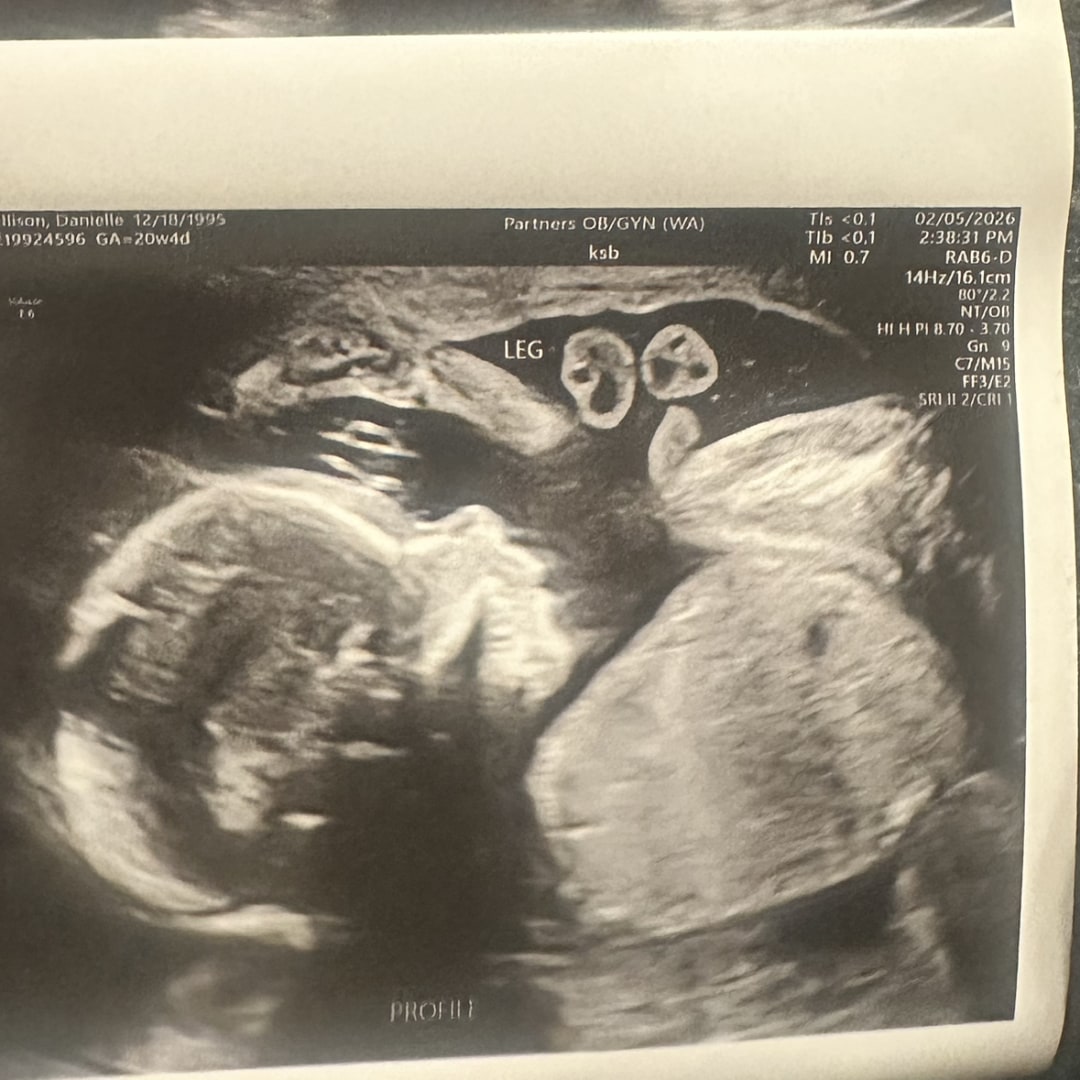

Ultrasound Pictures :)